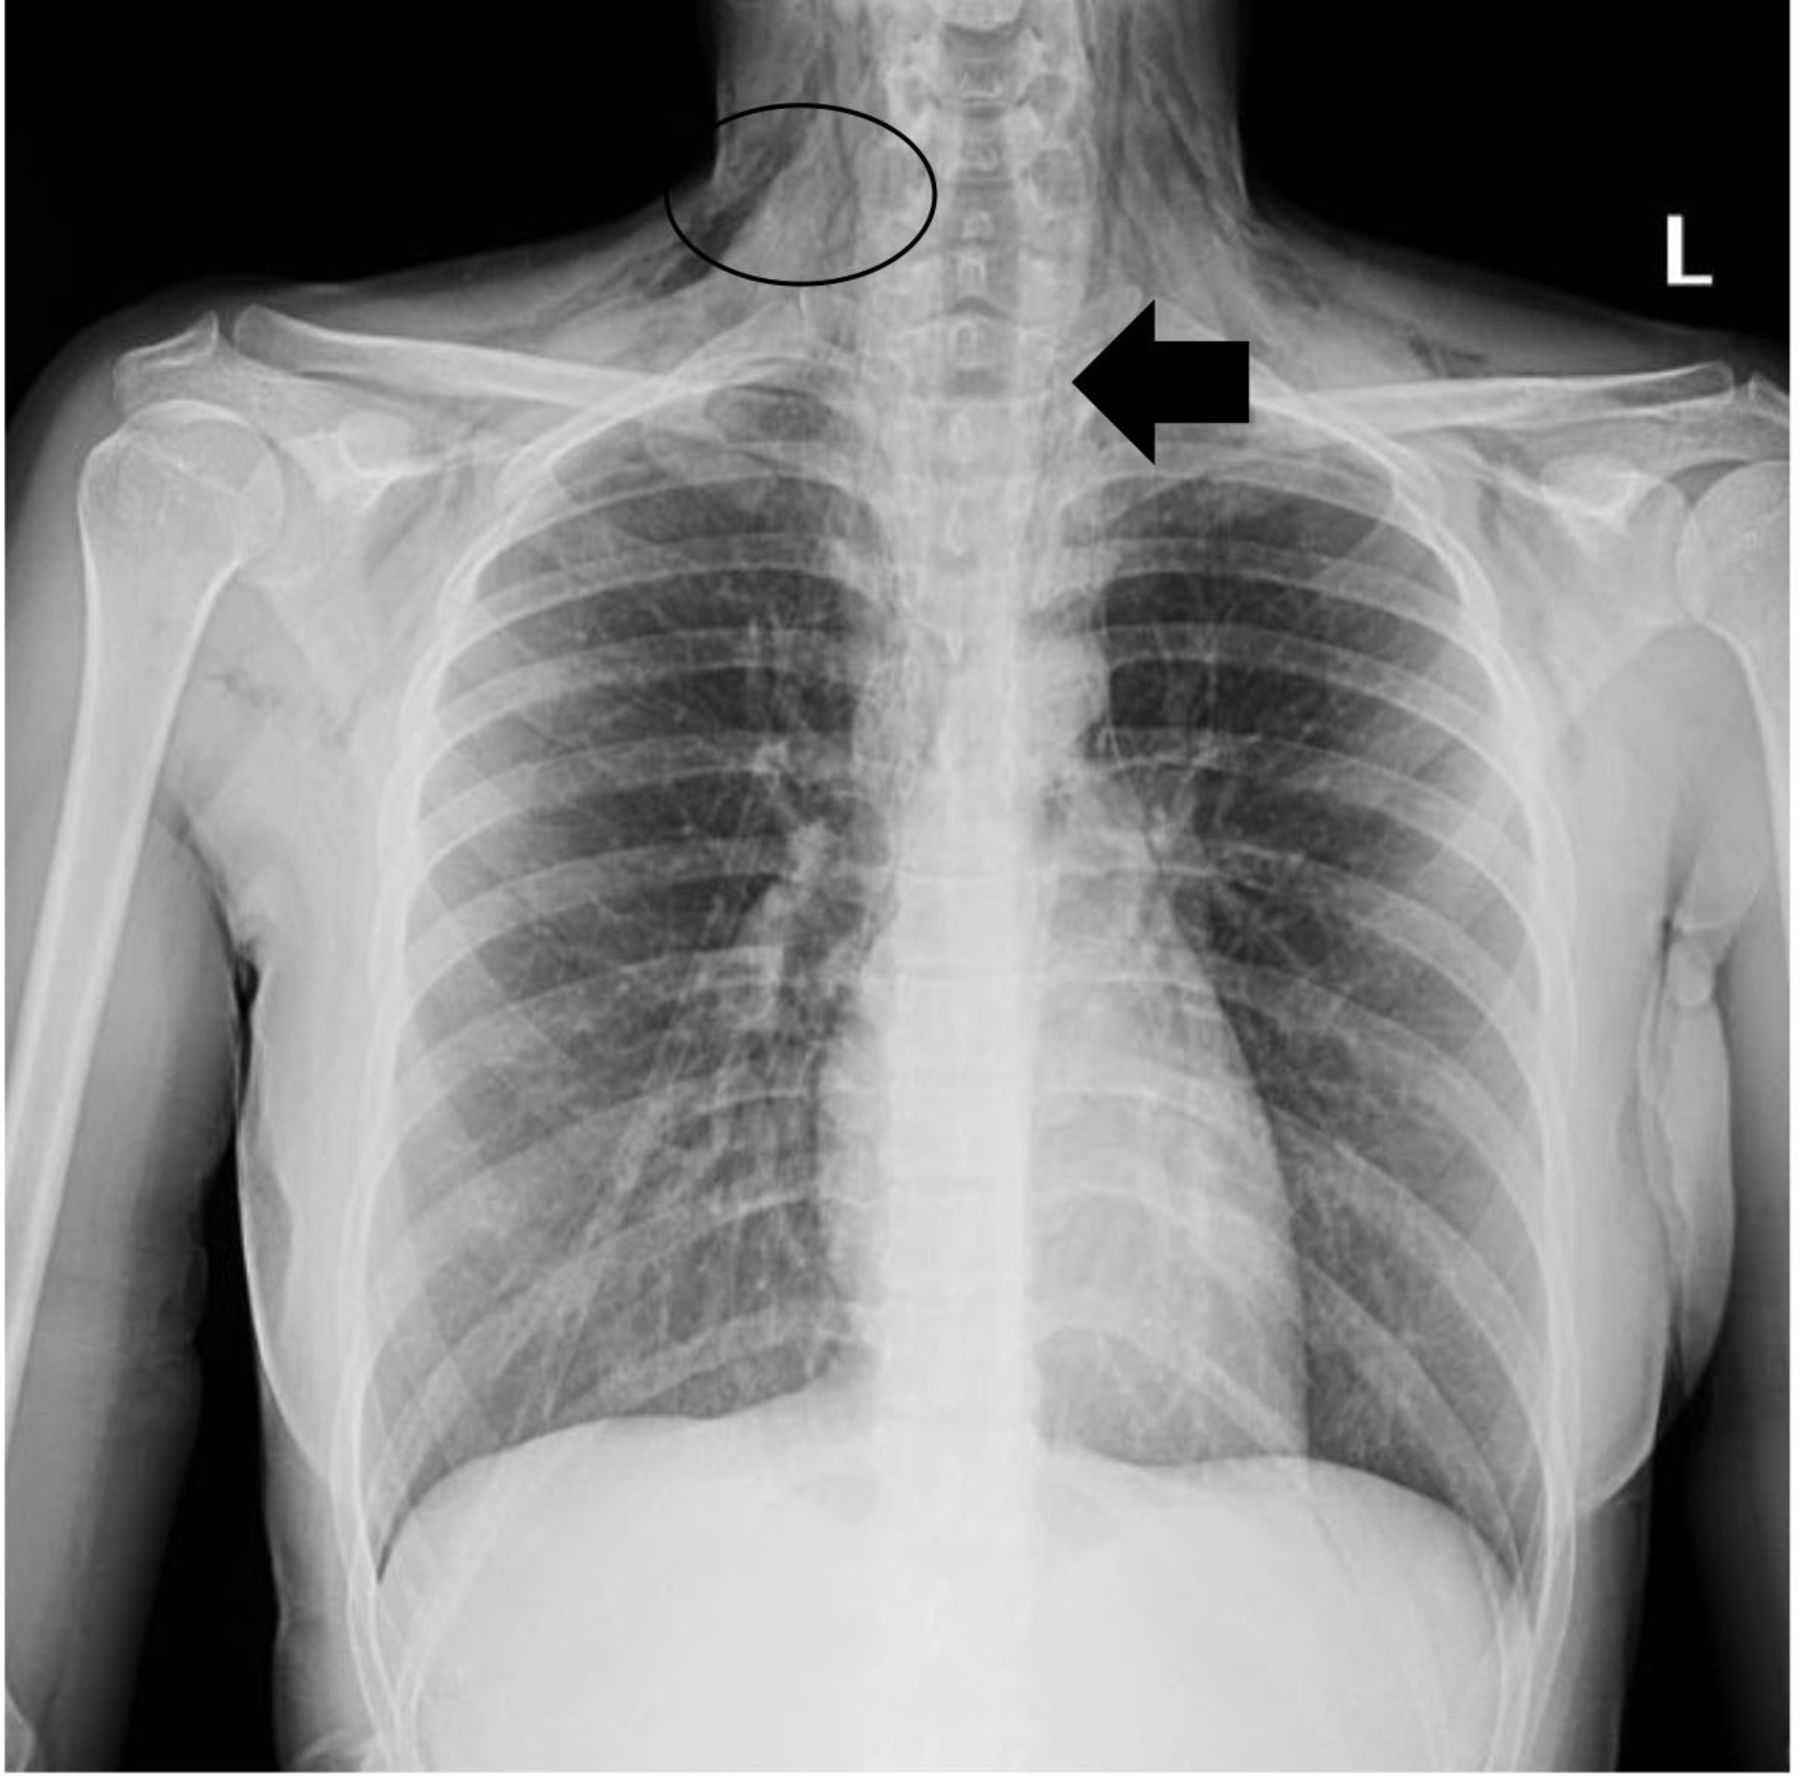

Что такое малоконтрастная рентгенограмма органов грудной клетки